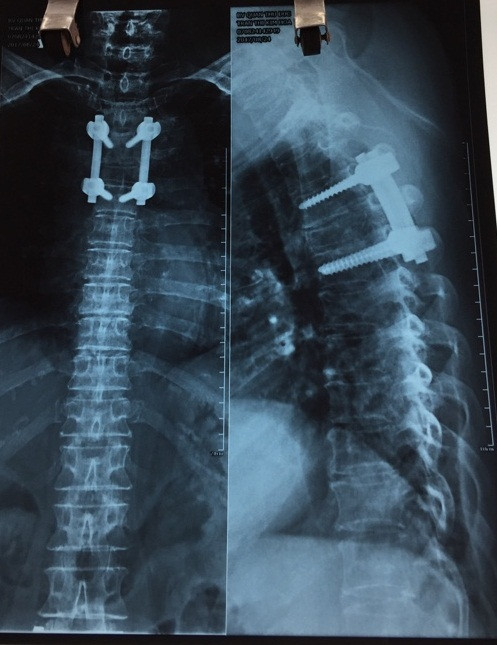

| Vị trí can thiệp cứu vận động cho cụ H. |

Phẫu thuật lần đầu giải phóng tủy ngực D4 bị chèn ép dưới kính vi phẫu. Phẫu thuật lần hai sau đó 10 ngày, bệnh nhân được lấy khối thoát vị và làm rộng ống sống lưng, đặt dụng cụ nẹp vít kết hợp bơm xi măng vào thân đốt sống giúp cố định và thay đĩa đệm nhân tạo L3-L4, L4-L5. Cả 2 cuộc phẫu thuật giải quyết chèn ép tủy diễn ra thành công. Sức khỏe cụ H. đã ổn định, có cảm giác trở lại, vận động được 2 chân, đi tiêu, đi tiểu bình thường; được chỉ định tập vật lý trị liệu tích cực để hồi phục khả năng đi lại.